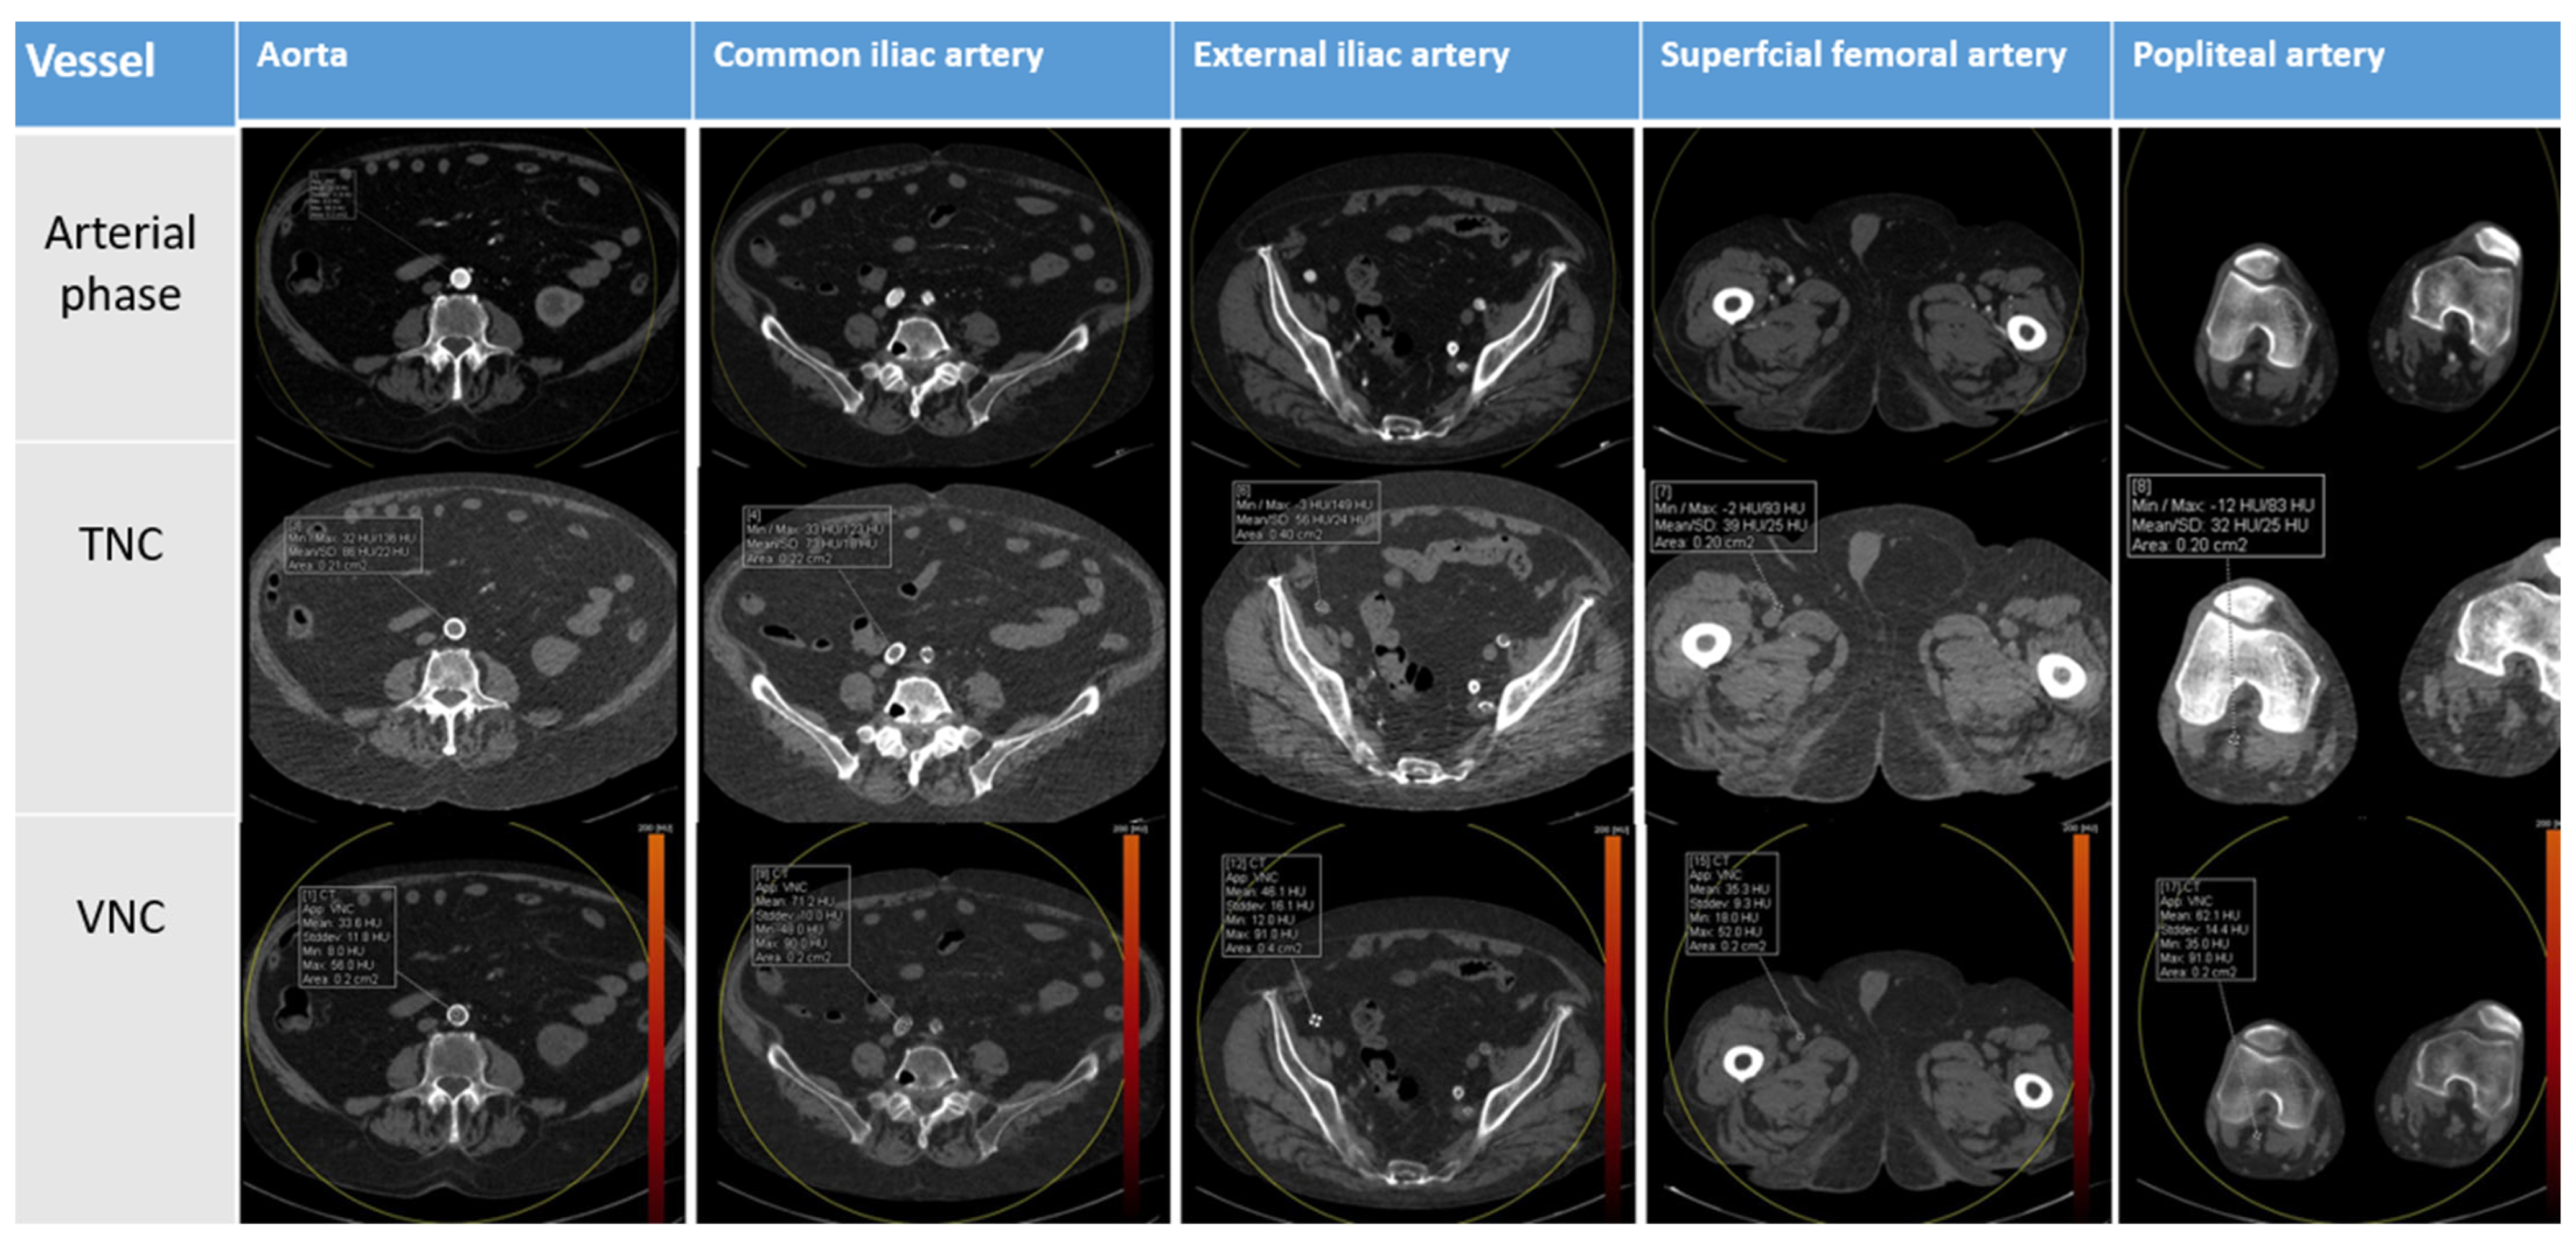

2. Materials and Methods

2.3. DE-CTA Image Reconstruction

2.4. Image Analysis

3. Results

4. Discussion